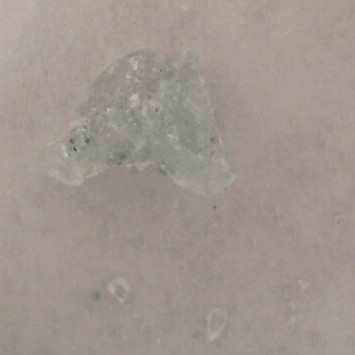

Fentanyl: NegativeBenzodiazepine: NegativeNotes: Vancouver, BC 01/18/2025 Category: OtherDescription: White PowderSold as: alpha-GPCResult: Fentanyl: NegativeBenzodiazepine: NegativeNotes: This sample shares similarities with our reference for alpha-GPC, but could not be confirmedVancouver, BC 01/18/2025 Category: DepressantDescription: Light Blue ChunkSold as: AlprazolamResult: Fentanyl: NegativeBenzodiazepine: PositiveNotes: The uncertain match in this sample shares similarities with a number of benzodiazepines, but can not be confirmed as such.Vancouver, BC 01/18/2025 Category: OtherDescription: White PowderSold as: ModafinilResult: Fentanyl: NegativeBenzodiazepine: NegativeNotes: Vancouver, BC 01/18/2025 Category: PsychedelicDescription: White PowderSold as: KetamineResult: Fentanyl: NegativeNotes: Vancouver, BC 01/18/2025 Category: DepressantDescription: White PowderSold as: PhenibutResult: Fentanyl: NegativeBenzodiazepine: NegativeNotes: Vancouver, BC 01/18/2025 Category: PsychedelicDescription: Light Grey CrystalSold as: MDMAResult: Fentanyl: NegativeNotes: Vancouver, BC 01/18/2025 Category: PsychedelicDescription: Colourless CrystalSold as: KetamineResult: Fentanyl: NegativeNotes: Vancouver, BC 01/18/2025 Category: OpioidDescription: White TabletSold as: HydromorphoneResult: Lactose Hydromorphone Uncertain Oil

Fentanyl: PositiveBenzodiazepine: PositiveNotes: Vancouver, BC 01/18/2025 Category: OtherDescription: White GranulesSold as: FasoracetamResult: Fentanyl: NegativeBenzodiazepine: NegativeNotes: Vancouver, BC 01/18/2025 Category: StimulantDescription: Colourless CrystalSold as: MethamphetamineResult: Fentanyl: NegativeNotes: Vancouver, BC 01/18/2025 Category: OpioidDescription: Green PebbleSold as: DownResult: Fentanyl: PositiveBenzodiazepine: NegativeNotes: Vancouver, BC 01/18/2025 Category: OtherDescription: White PowderSold as: PhenylpiracetamResult: Fentanyl: NegativeBenzodiazepine: NegativeNotes: This sample did not resemble our reference for phenylpiracetamVancouver, BC 01/18/2025 Category: StimulantDescription: White PebbleSold as: CocaineResult: Fentanyl: NegativeNotes: Vancouver, BC 01/18/2025 Category: PsychedelicDescription: Colourless CrystalCode: golden dogSold as: MDMAResult: Fentanyl: NegativeNotes: Vancouver, BC 01/18/2025 Category: StimulantDescription: Colourless CrystalSold as: MethamphetamineResult: Fentanyl: NegativeNotes: Vancouver, BC 01/18/2025 Category: StimulantDescription: White PowderSold as: CocaineResult: Fentanyl: NegativeNotes: The uncertain was too small to confirm; however, it shares similarities to multiple minerals and carbohydrates.Vancouver, BC 01/18/2025 Category: StimulantDescription: White ChunkSold as: Cocaine BaseResult: Fentanyl: NegativeNotes: Vancouver, BC 01/18/2025 Category: PsychedelicDescription: Light Blue PowderSold as: MDMAResult: Fentanyl: NegativeNotes: Vancouver, BC 01/18/2025 Category: StimulantDescription: White ChunkSold as: Cocaine BaseResult: Fentanyl: NegativeNotes: Vancouver, BC 01/18/2025 Category: UnknownDescription: Brown ChunkSold as: UnknownResult: Opium Uncertain Carbohydrate